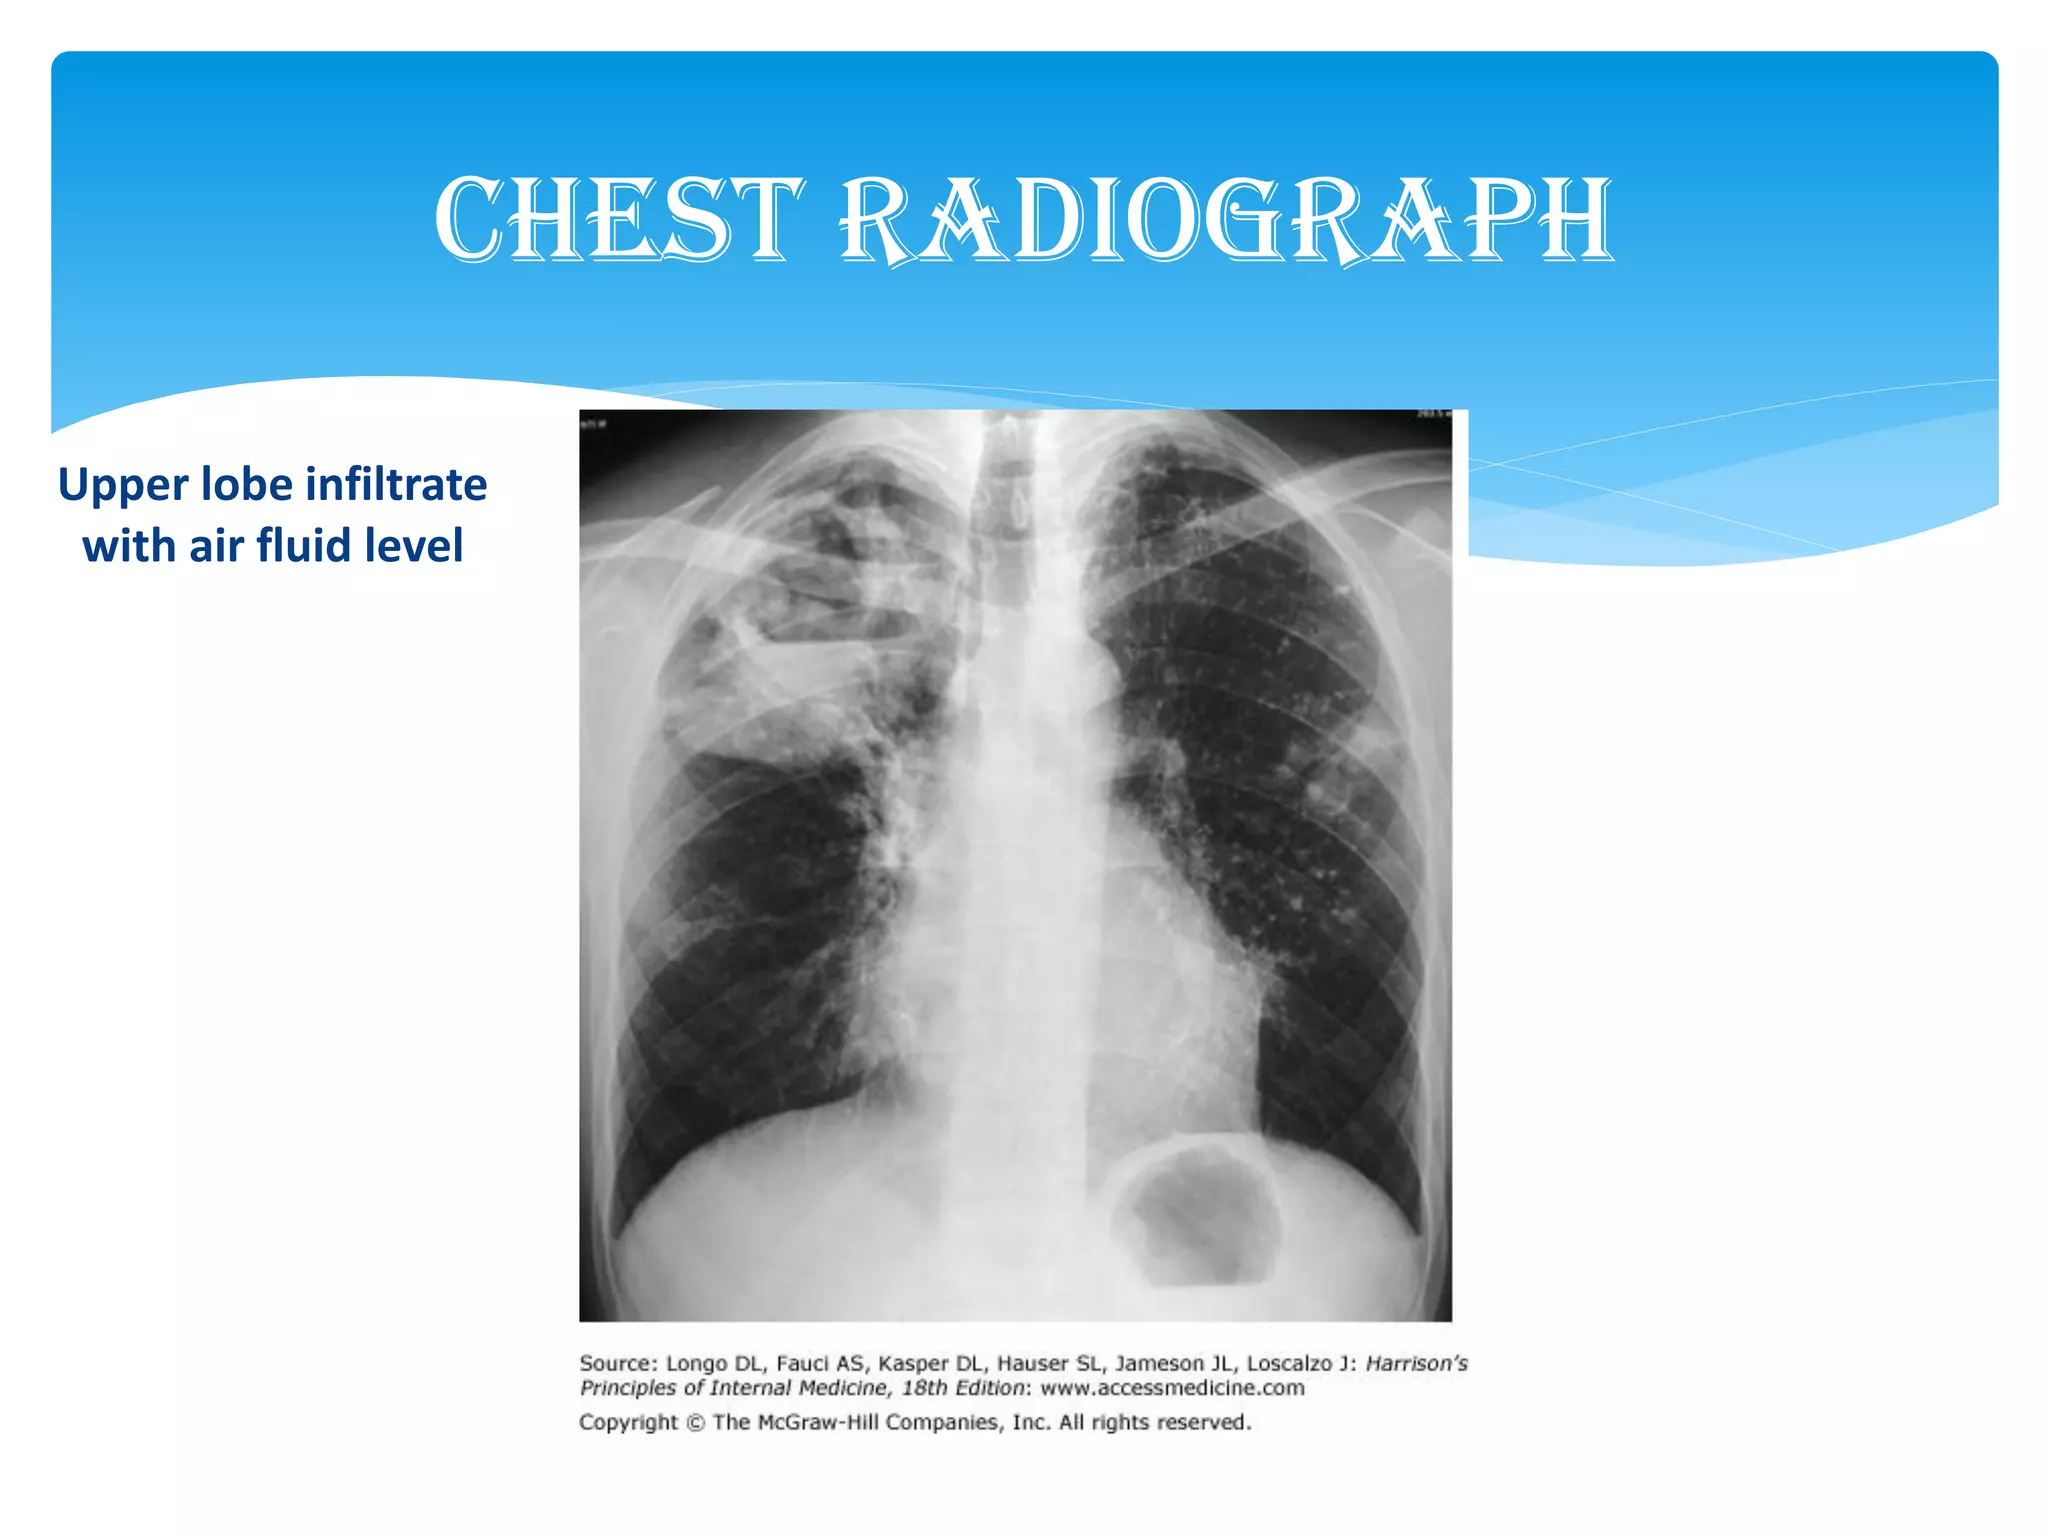

Chest Radiograph

Upper lobe infiltrate

with air fluid level